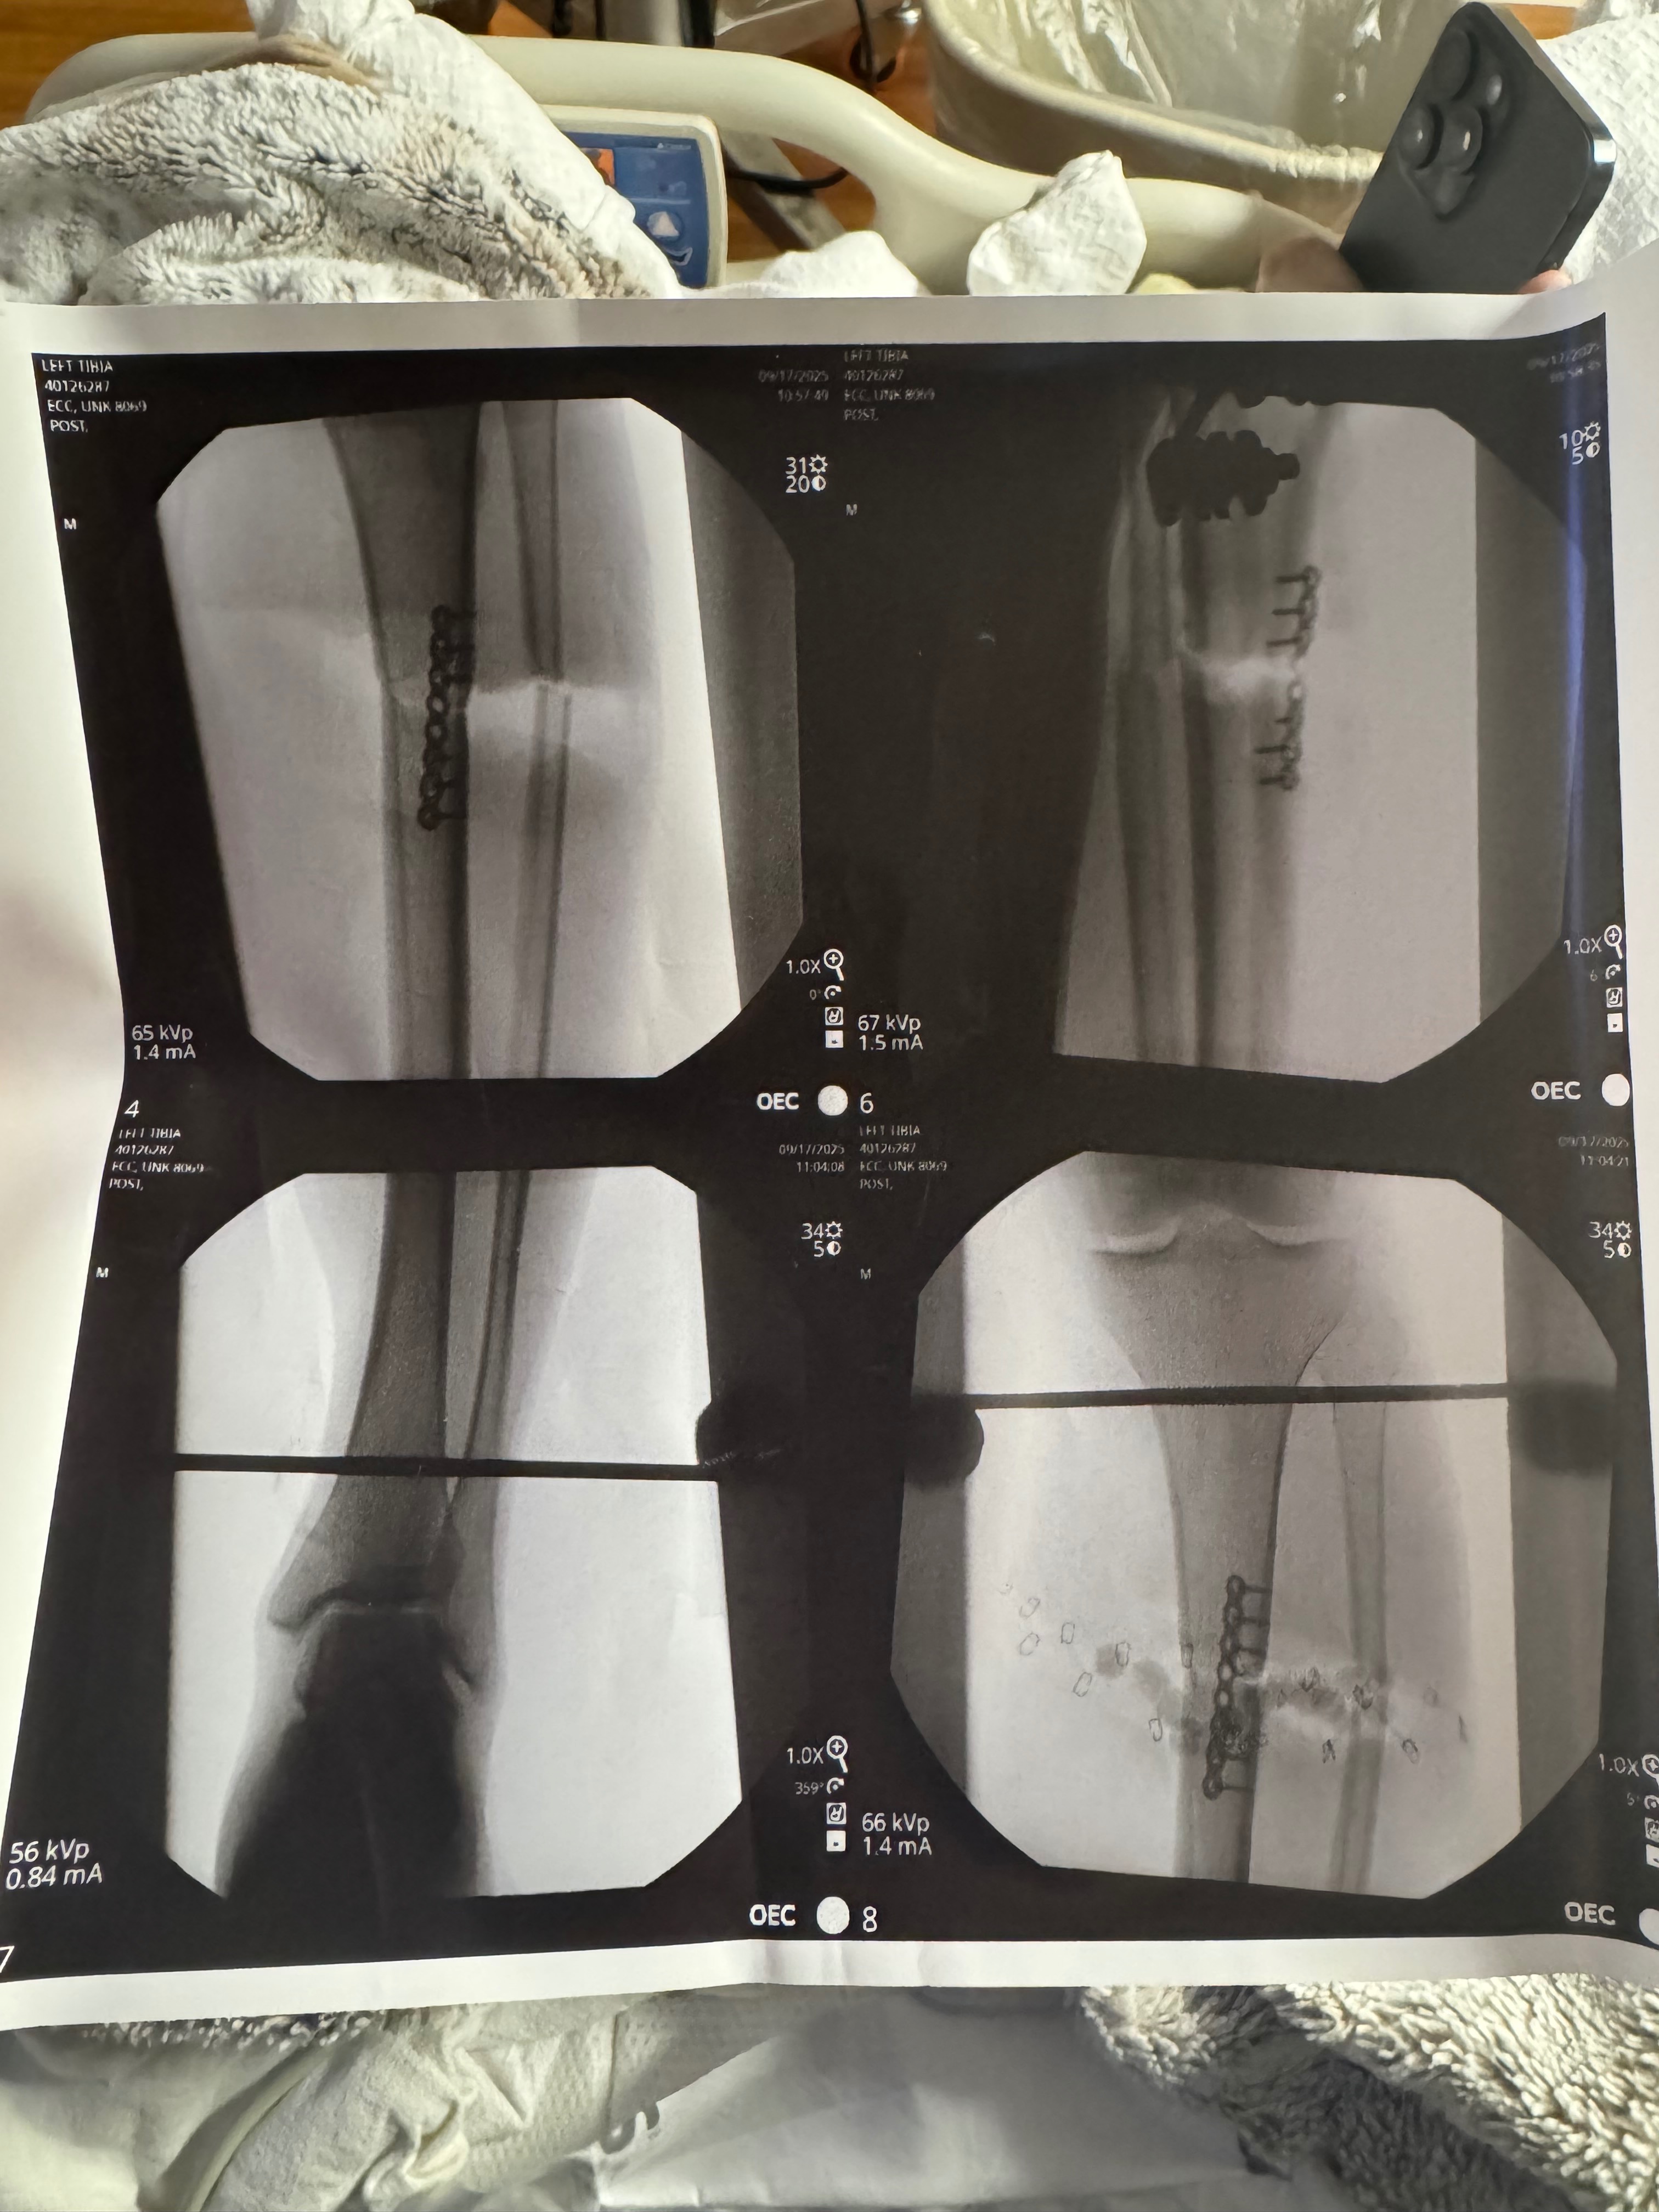

On September 17th, Gage was in a serious accident at work. A freak accident that resulted in both his tibia and fibula bones in his left leg being cut in half with a saw. Gage’s leg was literally hanging on by his calf muscles. He has had one surgery so far and is looking at 1, maybe 2 more surgeries ahead. Not to mention the months of physical therapy and mental rehabilitation from this traumatic injury.